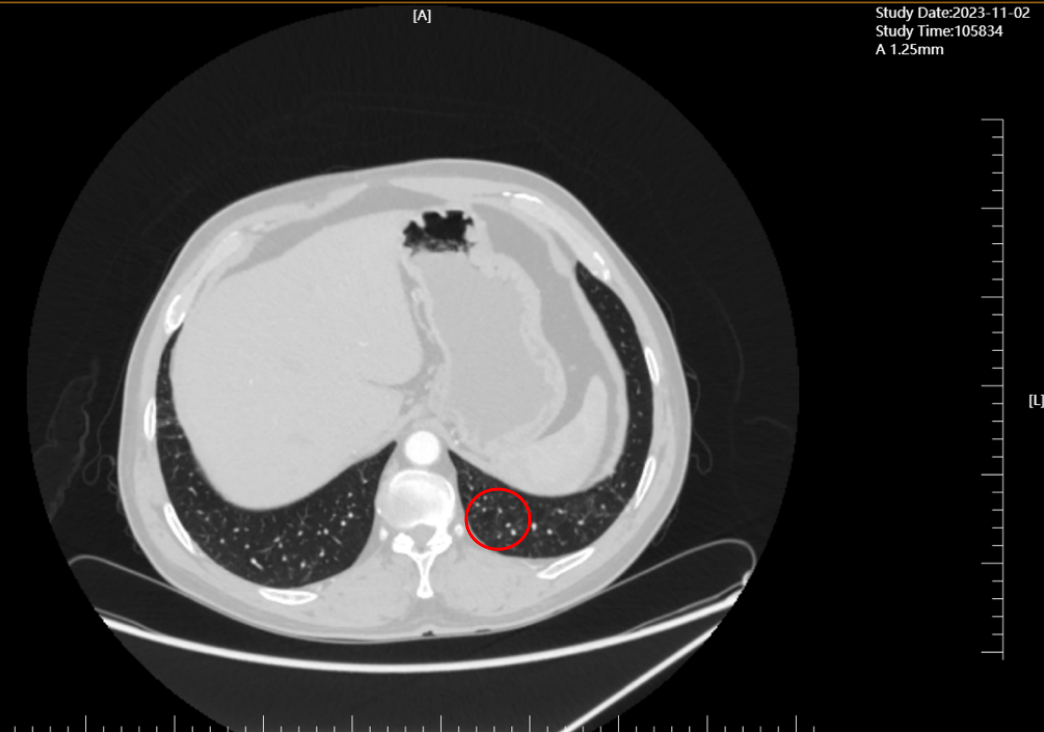

治疗期间依托科室影像诊断技术(高分辨率CT)、实验室检测技术(肿瘤标志物动态监测),建立“周度评估+月度复查”的技术监测体系:

2023年11月(联合治疗5周期),CT显示肺部原病灶大部分退缩为磨玻璃影,技术层面验证“肿瘤活性显著降低”;

2024年2月(单药维持3个月),经影像科与肿瘤科联合评估,达到完全缓解(CR)——这是晚期肺癌治疗中的“技术里程碑”,意味着体内可检测肿瘤病灶完全消失。